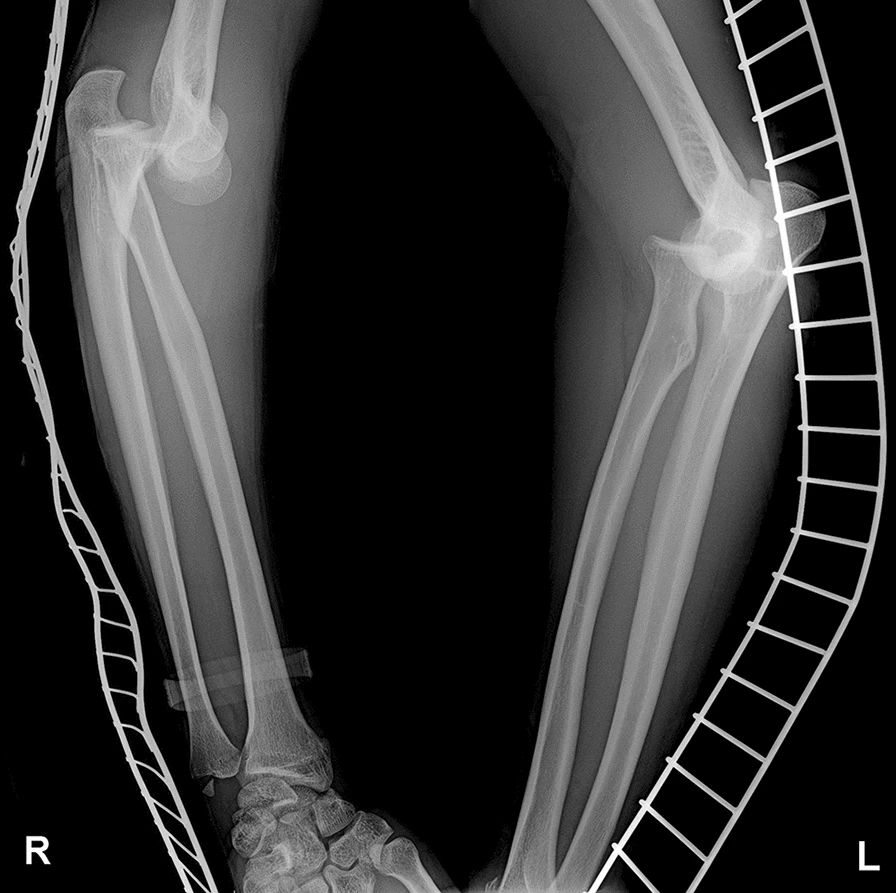

Rentgenový snímek obou poraněných loketních kloubů.